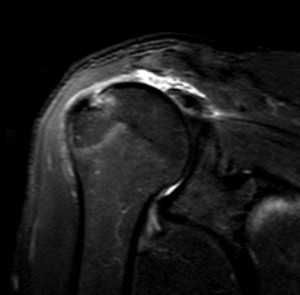

МРТ. Корональная Т2-зависимая томограмма с подавлением сигнала от жира. Полный разрыв сухожилия надостной мышцы.

При МРТ плечевого сустава косвенным признаком разрыва вращательной манжеты служит высокий сигнал на Т2-взвешенных от поверхности сустава до субакромиальной (субдельтовидной) сумки. Частичные разрывы чаще всего по передней поверхности сухожилия м.supraspinatus, реже примыкая к большой бугристости или сухожилия м. infraspinatus.

МРТ плечевого сустава. Т2-взвешенная корональная МРТ. Субакромиальное скопление жидкости - косвенный признак разрыва вращательной манжеты.